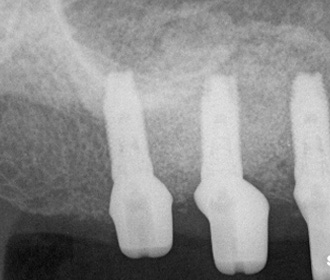

アトランティスシステムにより、ジルコニアアバットメントがCAD/CAMにより作製された。

アトランティスのガイドにより正確に位置決め可能。 -

ジルコニアアバットメント上に装着されたプロビジョナル、矯正治療は継続。